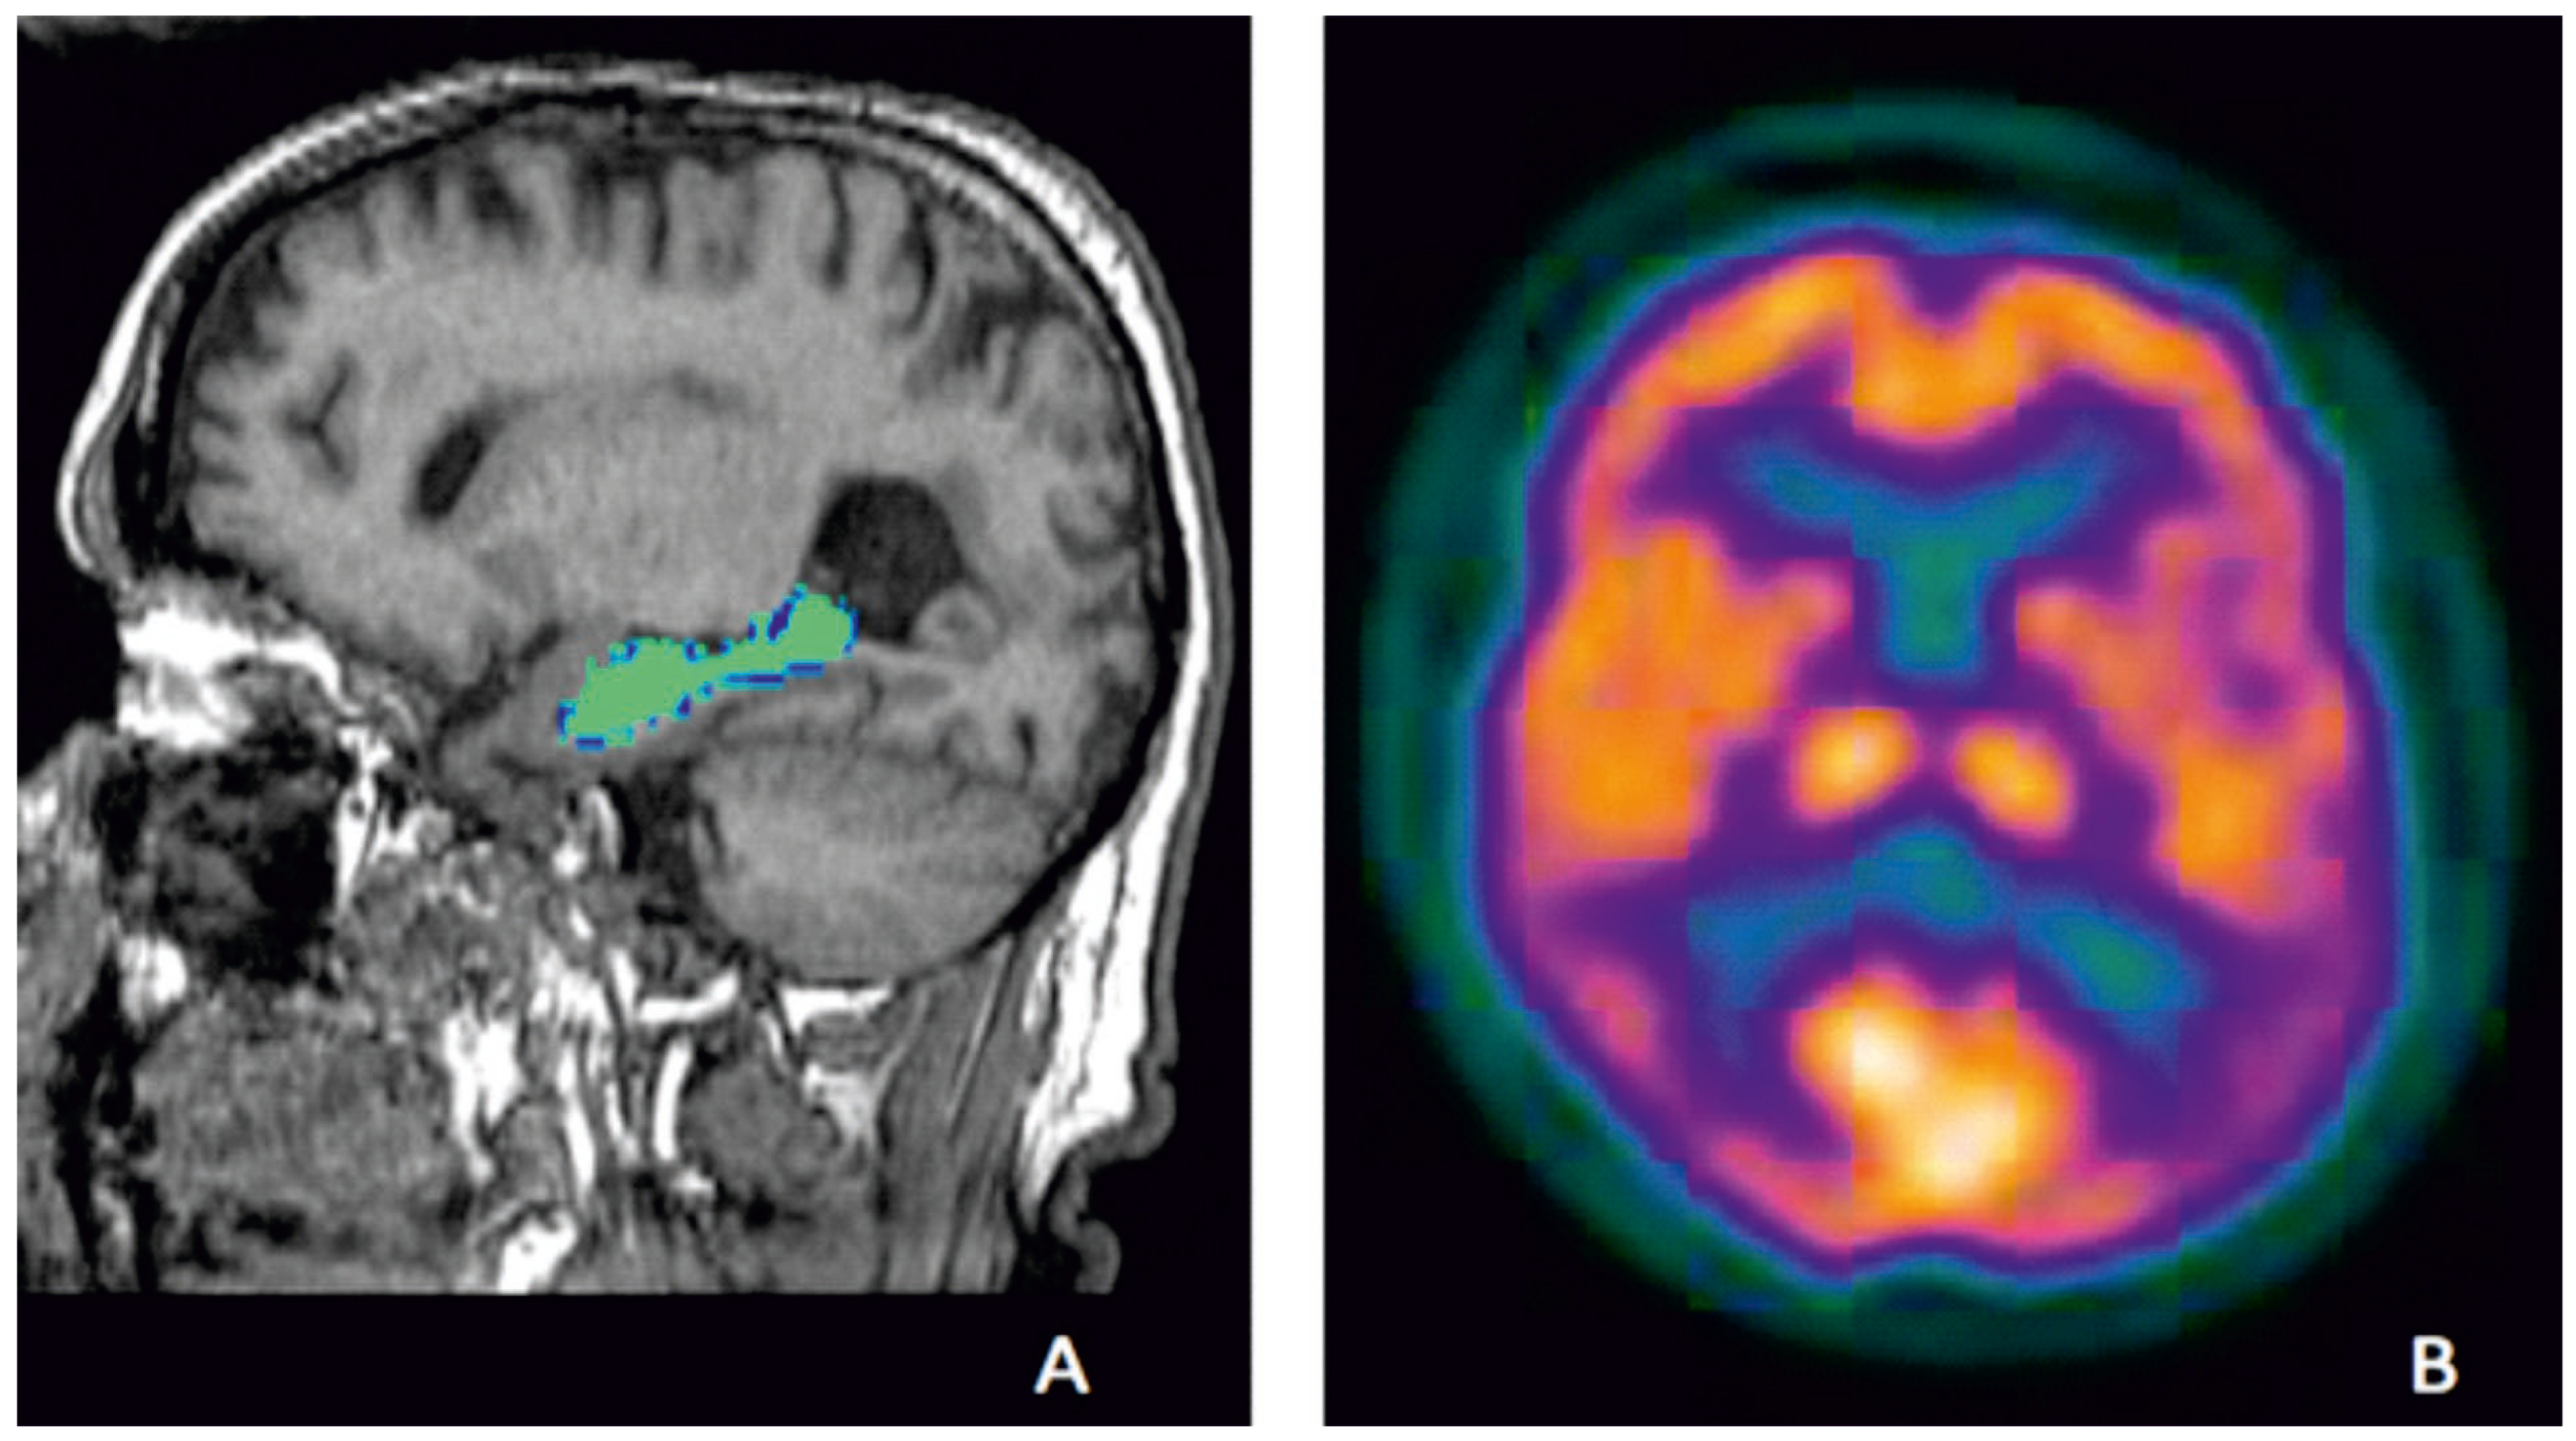

Figure 1.

Examples of established biomarkers in AD; hippocampal volumes on MRI of a participant from Aberdeen Birth Cohort 1936 study, illustrating hippocampal volume measurement which is highlighted in green (A) and temporo-parietal defects (violet) on FDG-PET showing hypo-metabolism in temporo-parietal region of a participant from an Alzheimer’s disease clinical trial who met research criteria for probable AD (B) (Courtesy—Alison D. Murray, University of Aberdeen).